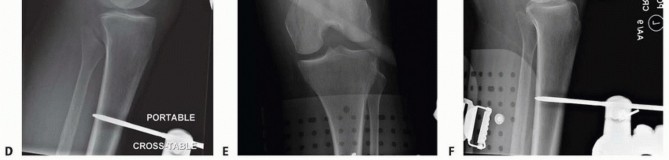

### FIG 5 • A-C. Patient with a spiral distal-third femur fracture that appears to be extra-articular. A. In the AP radiograph, the knee is not fully visualized. B. A dedicated knee AP radiograph shows the spiral distal-third femur fracture. Note the intra-articular injury and the gap at the fracture (arrows). C. Lateral view of the knee. Again note the coronal fracture of the medial femoral condyle (type B3). D-F. Plain radiographs of a patient with a grade II open distal femur fracture. G,H. Patient with a dosed femur fracture that was initially thought to be extra-articular. 470

### FIG 9 • Critically ill elderly polytrauma Jehovah's witness patient with left C1 distal femur fracture. A,B. Initial injury AP and lateral views. C,D. Due to extremely low hematocrit, external fixation was the only surgical option allowed to minimize blood loss. Radiographs in bridging external fixation. The AP shows excellent alignment but the lateral shows the expected extension deformity secondary to pull of gastrocsoleus complex. E,F. After 5 weeks in an external fixator, AP and lateral radiographs show callus formation (red arrows). Patient is now cleared for definitive surgical intervention. Antegrade intramedullary nailing has been described and can be used for distal fractures with a large enough distal segment to allow for two locking screws. Malalignment has been a problem, as has adequate fixation. 4, 8 Retrograde intramedullary nailing can be used in the following cases ( FIG 10): All extra-articular type A fractures greater than 4 cm from the joint. This minimal length of the distal femur allows for multiplanar interlocking in the distal fragment. Type C1 or C2 fractures where the articular fracture can be anatomically reduced closed or with limited exposure. Percutaneous screws are used for the articular injury. Periprosthetic fractures around a total knee arthroplasty with an “open box” femoral component Most surgeons prefer to use a long nail, but short supracondylar nails are available as well. Multiple-hole short supracondylar nails have fallen out of favor. Plate fixation ORIF with plates can be used for all types A and C fractures but is ideal for the following injuries: Very distal type A fractures within 4 cm of the knee joint All articular type C fractures, but always for C3 types Periprosthetic fractures about a “closed box” femoral component of a total knee arthroplasty The partial articular type B1 or B2 if an antiglide plate is needed Plate options (preferred to least preferred; fixed-angle devices preferred) Fixed-angle locking plates (percutaneous jigs are advantageous and allow for minimally invasive techniques) Variable-angle (polyaxial) locking plates—allow for “fixed variable locking” within a defined range. It is useful for distal fractures and allows for increased screw 473 trajectories to gain additional locked fixation in short segments, which may not be feasible with fixed-angle trajectory plates ( FIG 11).

### FIG 10 • A,B. AP and lateral radiographs of an elderly patient with multiple comorbidities with an extra-articular distal femur fracture (AO type A; an incomplete intercondylar split— red dashed arrow). C,D. Postoperative radiographs showing stabilization with retrograde intramedullary nail. E,F. One-year postoperative radiographs showing a healed fracture with some subsidence of the metaphyseal region and mild protrusion of hardware through the notch. Ninety-five-degree condylar screw Ninety-five-degree blade plate Nonlocking plates with or without medial support (medial plate or external fixation) Limited internal fixation Limited fixation with screws only can be used for partial articular type B, especially type B3. The amount of open reduction required depends on the adequacy of closed reduction techniques and obtaining an anatomic reduction of the joint surface. Headless screws are useful for type B3 fractures in which the screws have to penetrate the joint surface ( FIG 12). Countersinking the screw heads can also be performed. Biomechanics of fixation: implant considerations There has been concern that the newer locking plate constructs are too stiff, resulting in inconsistent and asymmetric callus formation. 9 Some clinical evidence show less callus formation with stainless steel plates versus titanium plates. 9 Conversely, a biomechanical study has not shown a significant difference mechanically between constructs of stainless steel LISS plates with bicortical screws or titanium LISS plate with unicortical screws.1 474